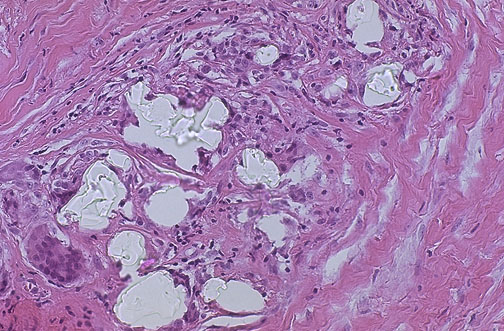

| Microscopic examination of the fibrous capsule from a silicone breast implant will often reveal the refractile silicone material as shown here, because this material gradually leaks out. There is a foreign body granulomatous response. This has not been shown to be associated with systemic disease, such as autoimmune disease. The fibrosis around a breast implant may produce deformity and pain in some women. Rupture is uncommon. |